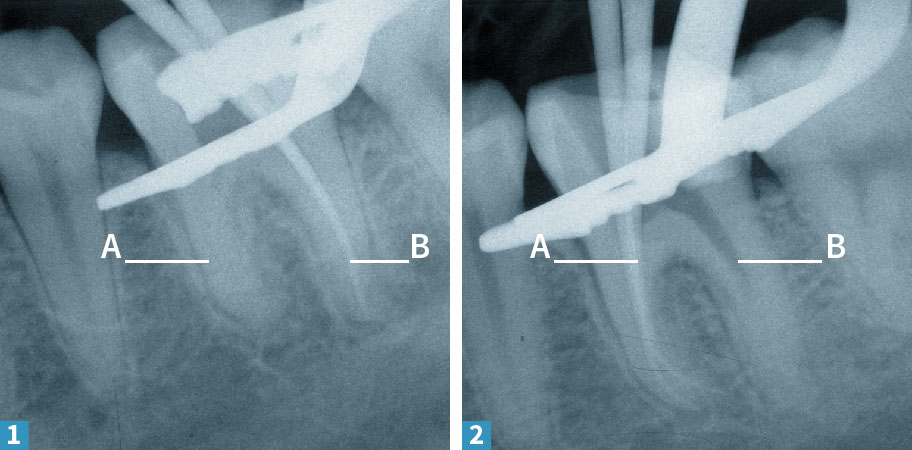

1, 2 Nun wird das Kanalsystem verschlossen. Das Wurzelfüllmaterial besteht hauptsächlich aus Guttapercha, einem besonderen Wachs, und Kleber. Vor der abschließenden Füllung wird der Sitz der Guttaperchastifte in den Wurzelkanälen mit Röntgenbildern kontrolliert – geprüft wird hierbei, ob die als dicke, weiße Striche zu erkennenden Guttaperchaspitzen bis ans Ende der Zahnwurzel reichen.

1, 2 Jetzt werden die beiden Wurzeln mit Ihren insgesamt vier Kanälen mit der Guttapercha und dem Kleber gefüllt. Als erstes wird die breite Wurzel (B) behandelt und mit einem Röntgenbild kontrolliert. In der Tiefe sind es noch zwei getrennte Füllungen, weiter zur Zahnkrone hin wird daraus eine breite.

3 Das Röntgenbild dient der Kontrolle dieses Arbeitsschrittes.